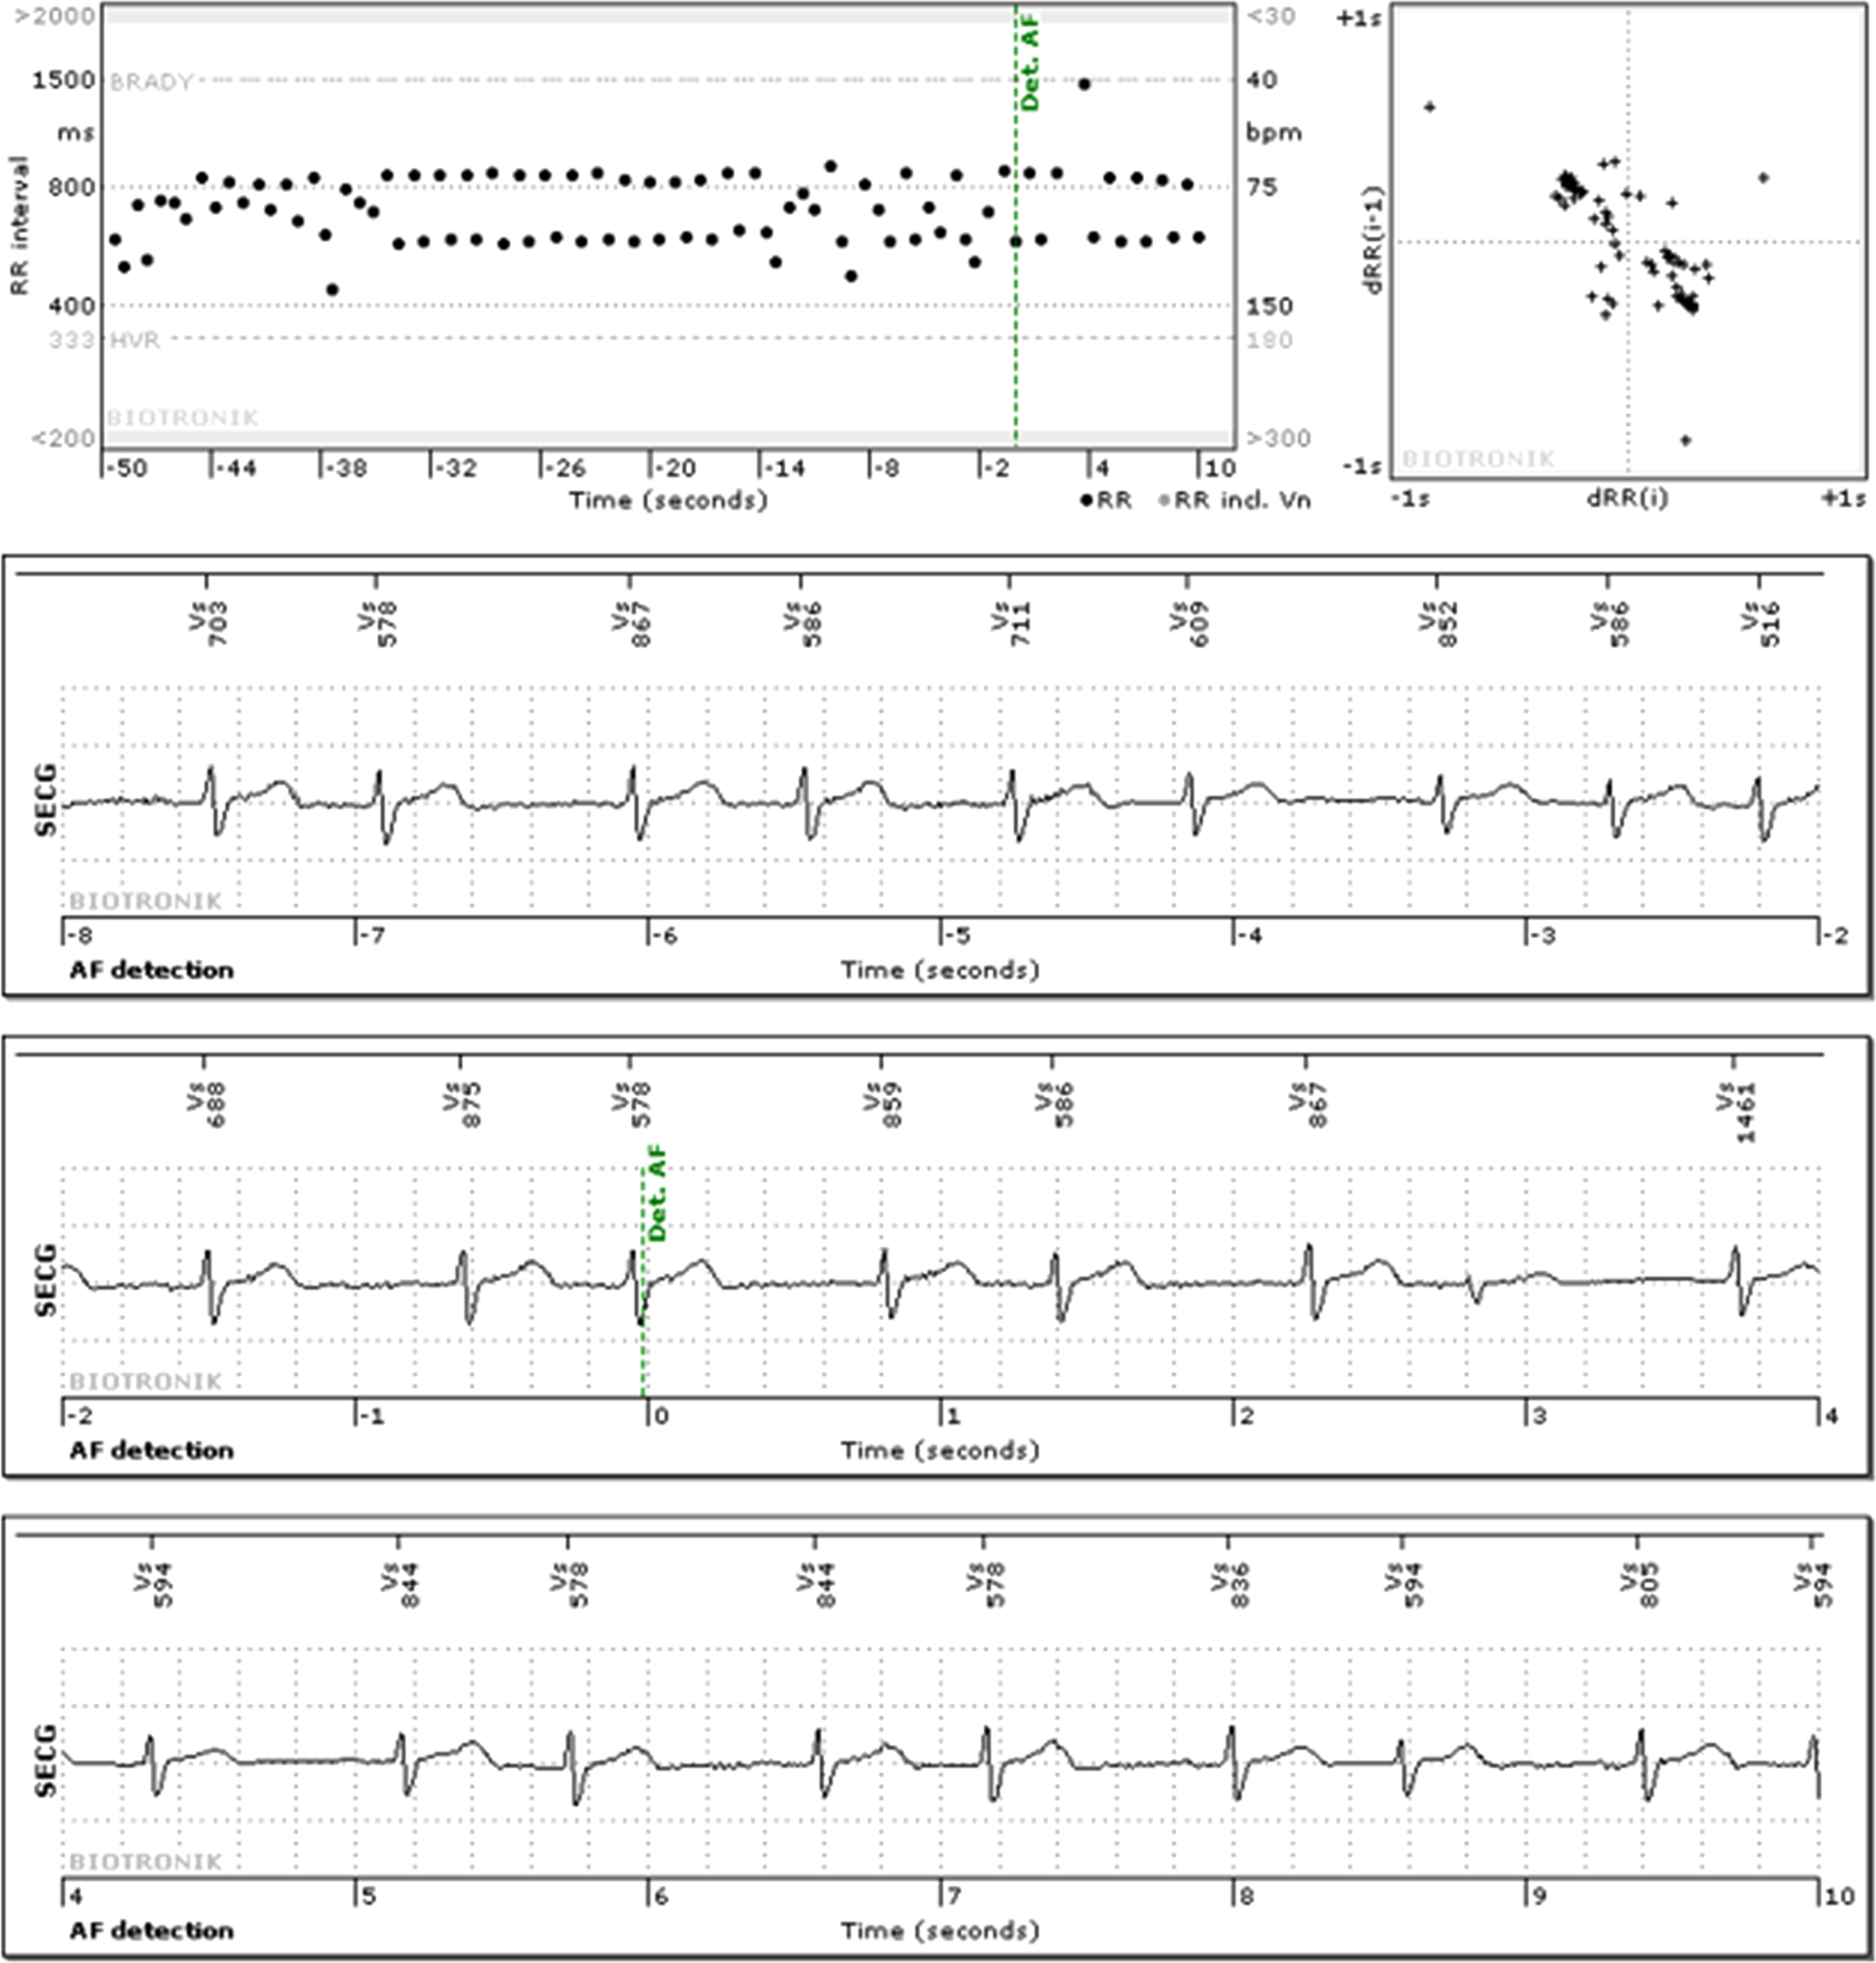

The most common events detected by the ICM were AF (36.1%) and bradycardia (34.9%) (Table 2). Sudden rate drop was observed least often (1.4%). SmartECG filtered 42.8% of all sECGs (Table 2). An example of an incorrect “AF” detection filtered by SmartECG is shown in Figure 1. The type of arrhythmia recognized by SmartECG as incorrect was most commonly pause (85.6% of events were filtered) and least frequently was bradycardia (28.6% filtered). By using the SmartECG algorithm, the number of sECGs per patient-year was reduced from 147 to 84 (Table 1).

Figure 1

Example of an sECG with an “AF” detection, classified as false detection both by the clinical board and SmartECG.